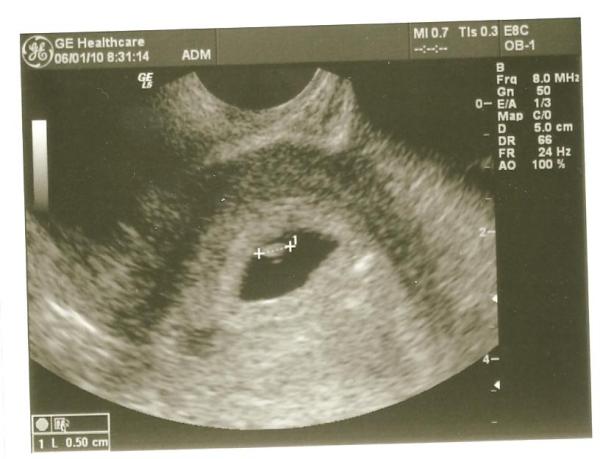

Lacinak telefonon mondtam meg, ...elkezdett nevetni és 100szor elmondta, hogy 3?!?!?!?

aztán kijelentettem, hogy én többé nem megyek nélküle uh-ra, mert mindig kiderül olyankor, hogy eggyel többen vannak...még két egyedül végig aszisztált uh, és kosárcsapat lesz a pocimban

nem találok 3as ikres vonalzóóóót

így petezsákokra osztottam őket